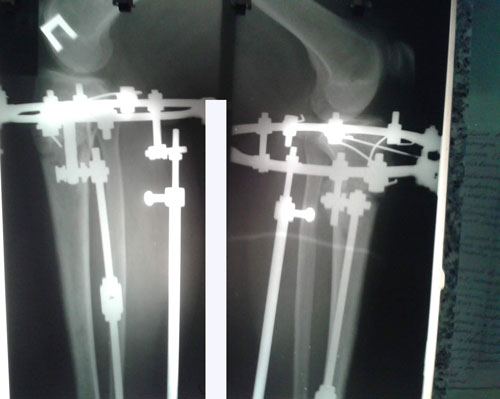

Re: Терачина♥♥♥

Дата операции 03.12.2015г.

Дата снятия аппаратов 09.03.2016г.

Срок лечения 95 дней.